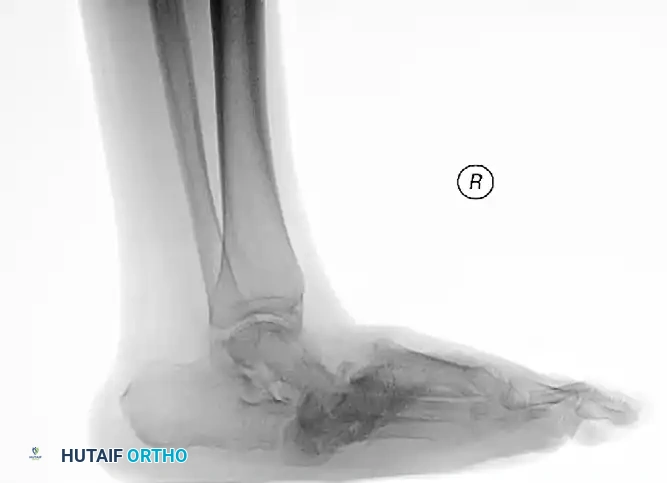

The following preoperative and postoperative radiographs demonstrate the successful application of augmented fixation in a young diabetic patient with a severe bimalleolar fracture-subluxation:

FIGURE 85-25 A and B: Preoperative radiographs of a highly unstable bimalleolar ankle fracture-subluxation in a 19-year-old man with a 12-year history of insulin-dependent diabetes mellitus.